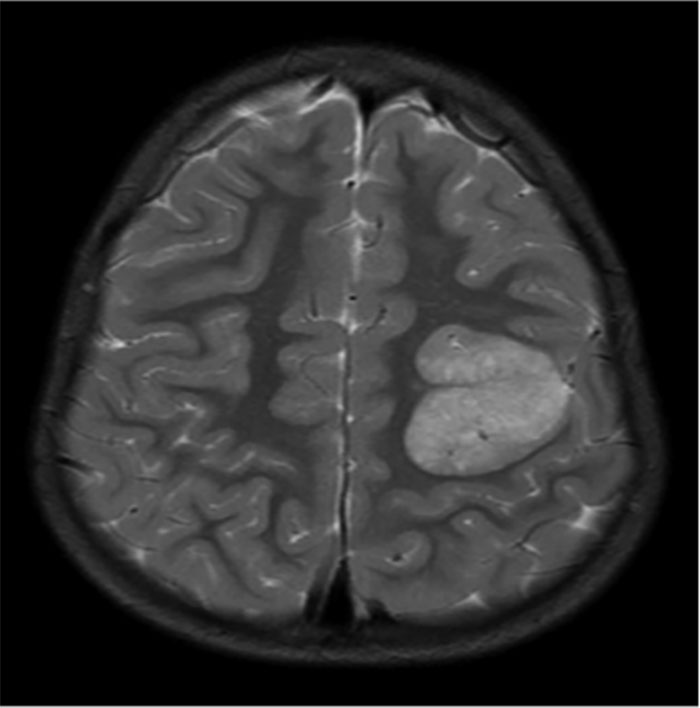

Back in 1990 was completing a group autopsy in an advanced human anatomy class. 85 year old patient had a tumor in her brain. It was the size of a Golfball on her right lobe. Unknown to her prior to death, her physician. Died in her sleep naturally. The tumor was not malignant but most likely caused some wicked headaches along with other symptoms. The stuff you find. The body is a wonder.

I actually had two strokes without knowing. I had an MRI because of a sudden weakness in my right hand and they showed up like that tumor above on my MRI. One on each side of my brain, both about the size of a quarter. The doctor said the white spots were the dead tissue in my brain. This was years ago and today I have some weakness in my left leg which my neurologist attributes to one of those strokes even though I had no recognizable symptoms at the time. And the hand weakness went away and we never found out it's cause.